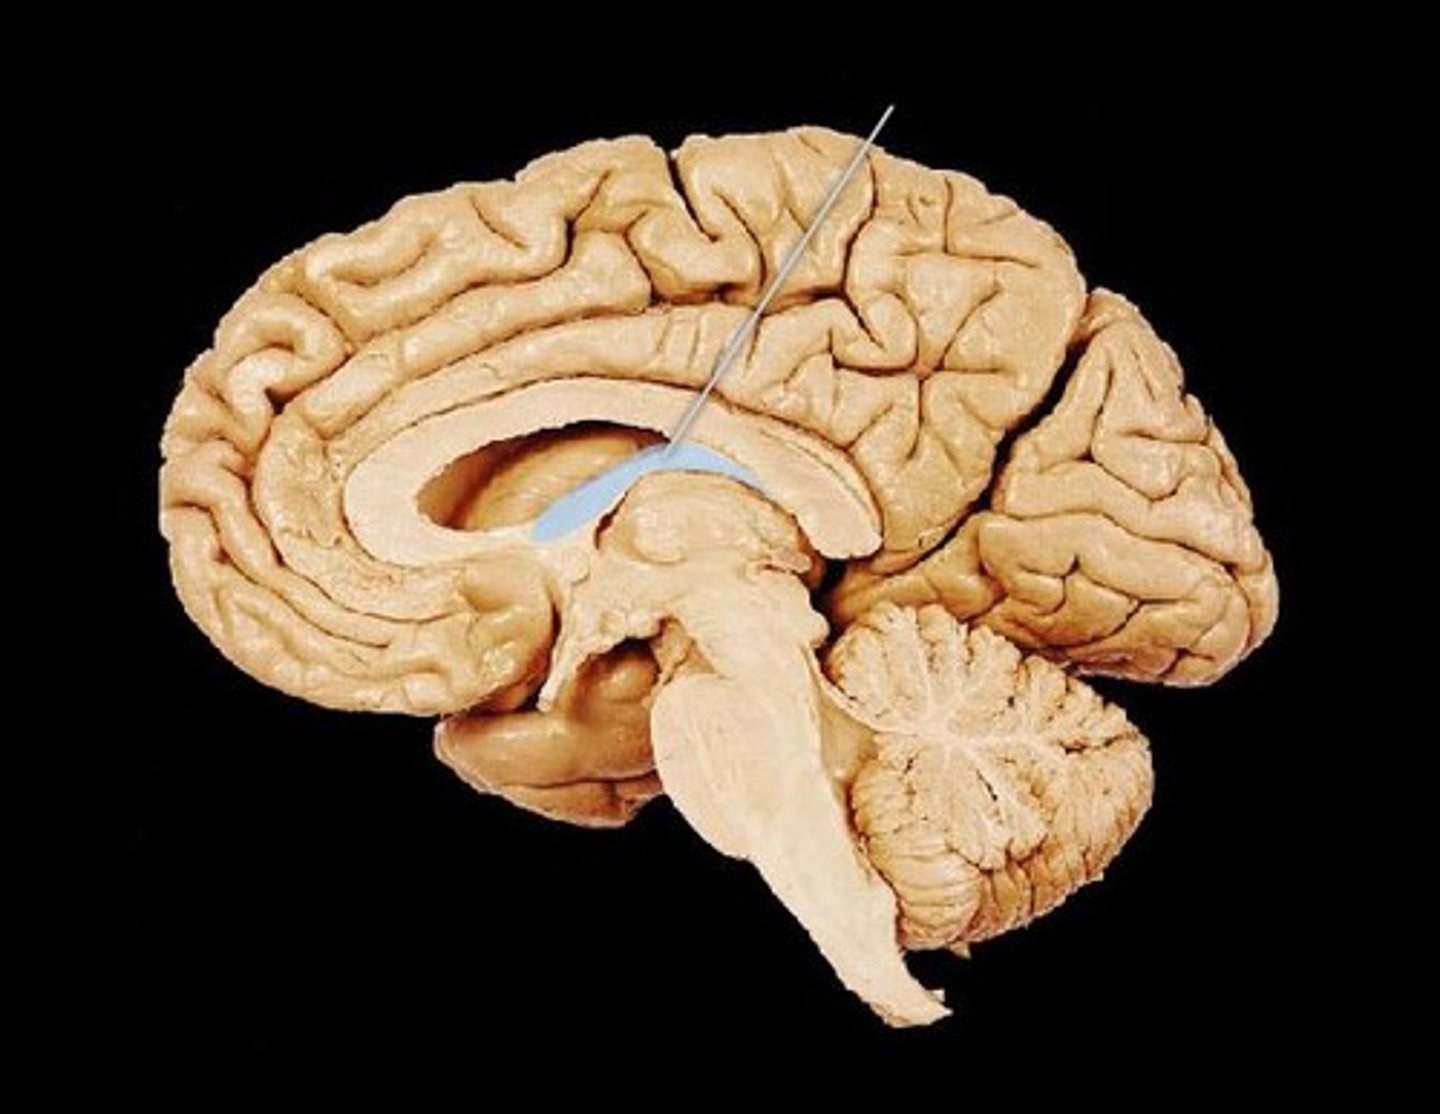

MIdsagittal View of brain

Fornix